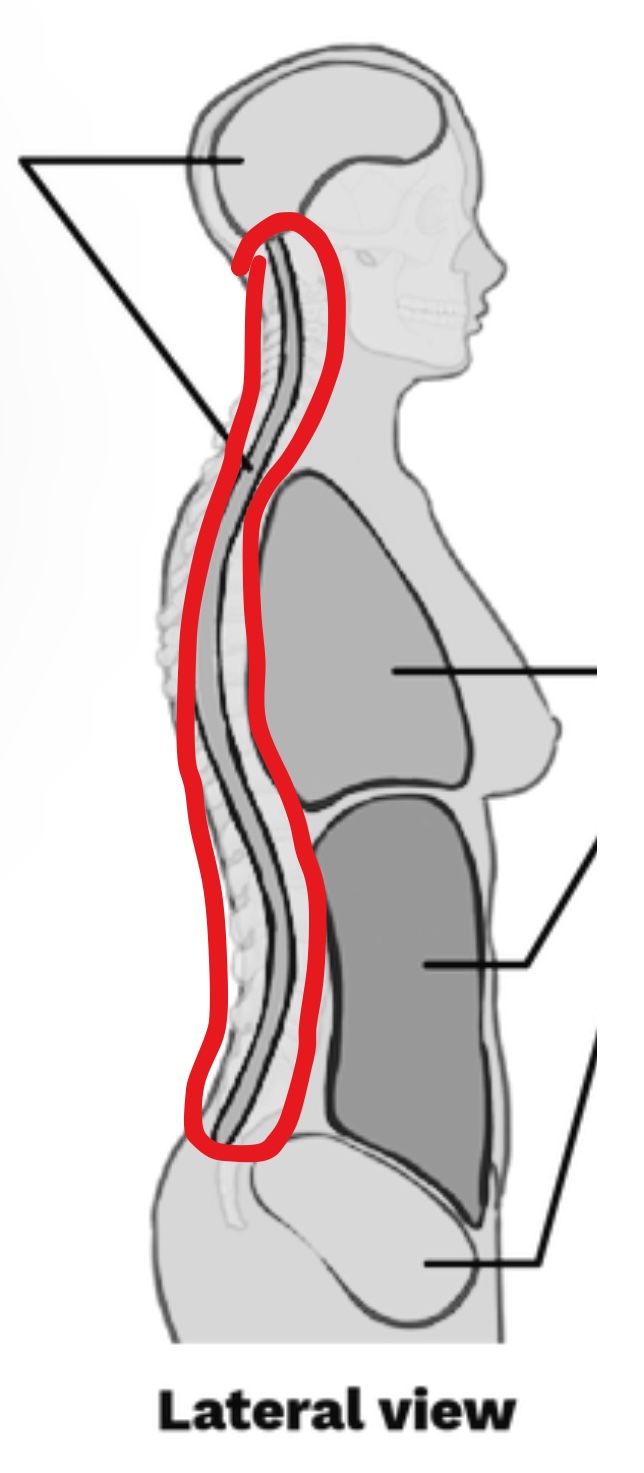

What cavity is this?

Spinal Cavity